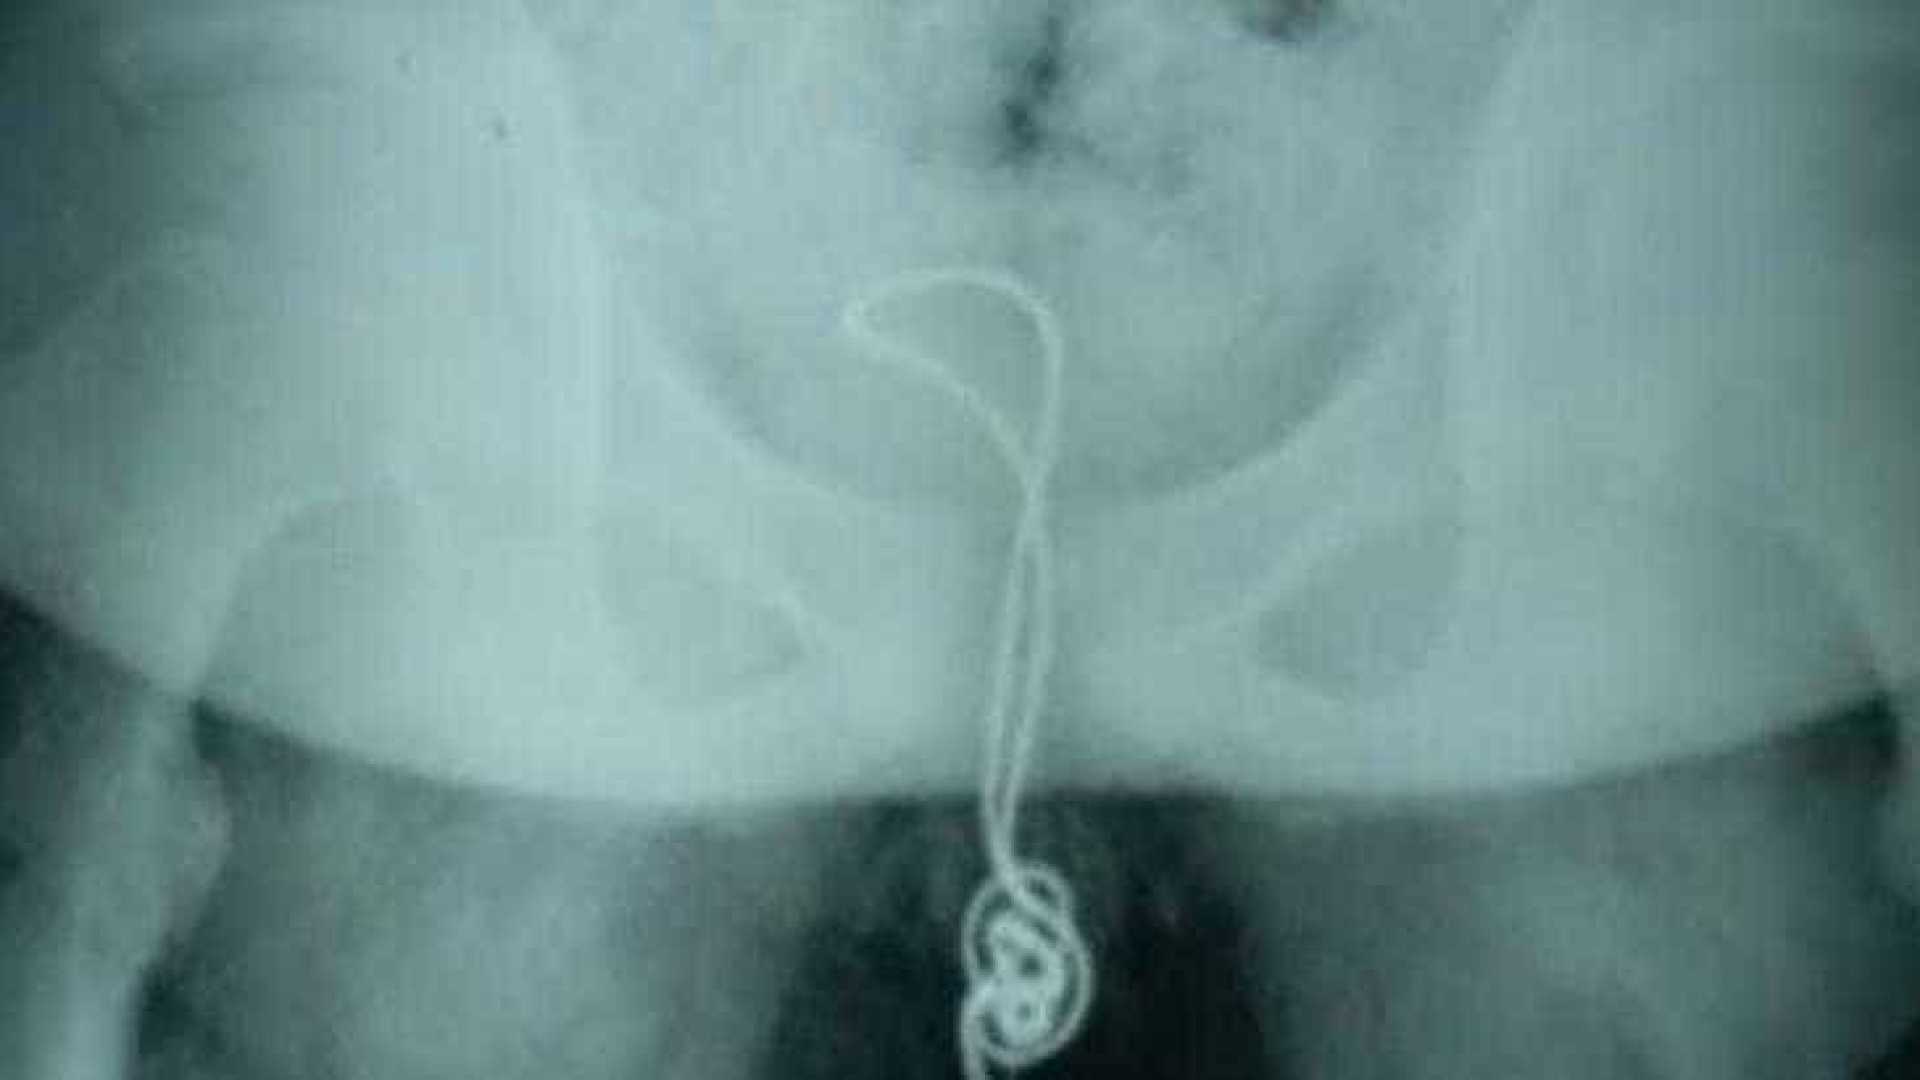

Rapaz inseriu o objeto em seu órgão genital 'por curiosidade' e não pôde removê-lo

O homem foi submetido a uma cirurgia por seis horas para remover as barras